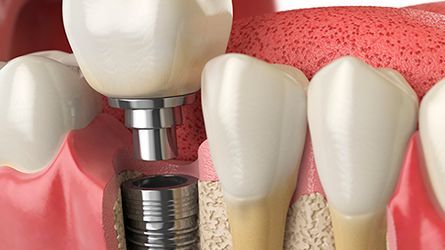

Single Dental Implants

Dental Implants Offered by Our Hamilton Dental Implant Specialists: